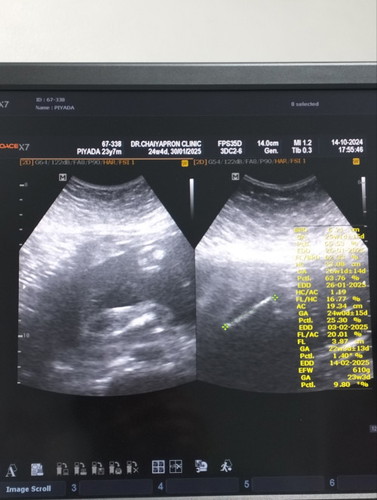

แม่ๆคิดว่าน้องเป็นผญ.100%มั้ยคะ

ผู้หญิงชัวร์มั้ยคะพอดีอยากเริ่มเตรียมของแล้วแต่กลัวจู๋โผล่😆 #ทีมมกราคม

ถ้าคุณแม่กลัวว่าจะเป็นชาย แนะนำเลือกซื้อเสื้อผ้าของใช้แบบทั้งหญิงและชายใส่ได้ คะ บ้านนี้กังวลอยู่เหมือนกัน หมอบอกผู้หญิง แต่กลัวมีจู๋โผล่มา😂 #ทีมมกราคม68

เห้นเป้นกลีบ ผญ.คะ

แม่ว่าผญค่ะ😍😍